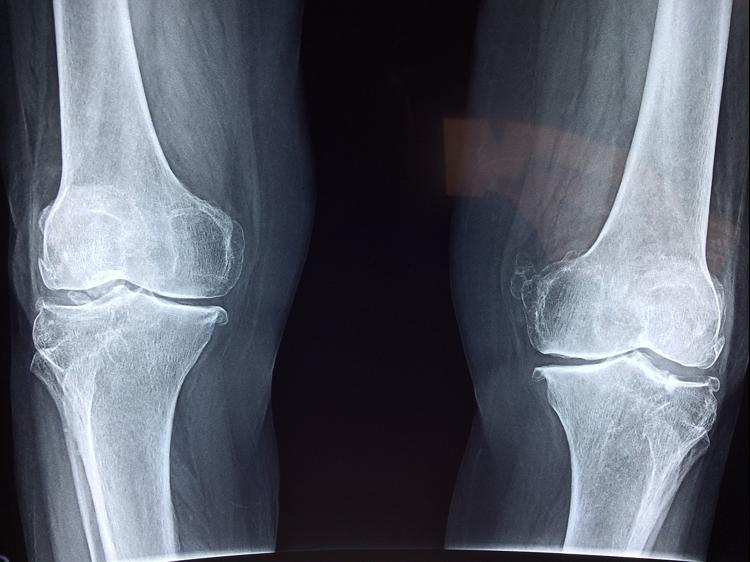

膝关节牵涉痛:神经通路的信号干扰

膝盖牵涉痛是股骨头坏死的特殊表现。这种疼位置模糊、和活动无关,做膝关节影像学检查也没发现器质性病变。研究证实,这种“疼痛转移”现象,源于髋膝关节的传入神经在脊髓L2-L4节段交汇。可以试着分析疼痛特点:记一下疼了多久、什么情况会诱发、有没有伴随症状,如果出现持续钝痛且放射到膝盖,要进一步检查。